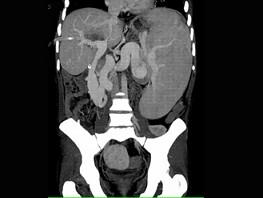

下列图像最可能的诊断是 ( )A.脂肪肝B.肝囊肿C.肝血管瘤D.肝脓肿E.肝炎肝硬化

问题 下列图像最可能的诊断是 ( )

选项 A.脂肪肝 B.肝囊肿 C.肝血管瘤 D.肝脓肿 E.肝炎肝硬化

答案 D